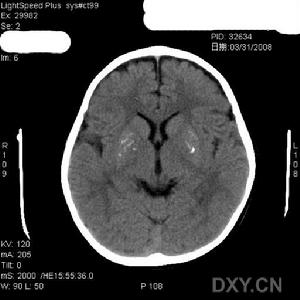

蒼白球黑質紅核色素變性2.MRI檢查T2WI示雙蒼白球外側低信號內側有小的高信號稱為“虎眼征”(eyeofthetiger)。